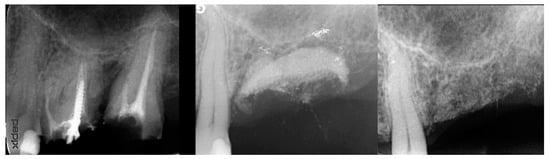

The patient returned at 10 weeks post-2nd-implant placement and a screw-retained restoration was placed on the 1st molar and a radiograph was obtained (Figure 13, left). Impressions were obtained and the restoration on the 2nd molar was placed at a subsequent appointment. Soft tissue was healthy at placement of the restoration on the 2nd molar and no marginal inflammation was noted at either site (Figure 14, left). Soft tissue at the 1-year recall remained healthy and lacking in inflammation (Figure 14, middle). At a 2-year recall, a radiograph was obtained and bone was noted to be stable at both implants (Figure 13, right). Soft tissue at the 2-year recall remained stable and no change in marginal position was noted compared to initial restoration placement (Figure 14, right).

Figure 13.

Radiograph at 10 weeks implant integration at the 2nd molar (left) and two years following restoration of the implant at the 2nd molar showing the improved vertical regeneration between the implants (right).